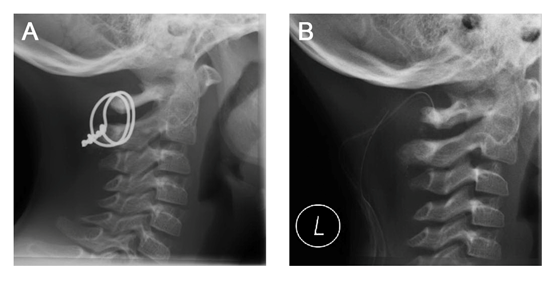

Examination showed a glascow coma score (GCS) of 15 with pupils equal, round, reactive to light and accommodation. He was responsive and alert on scene but couldn’t remember what has happened. The primary survey showed no disabilities or signs of head, chest, abdominal, pelvic or extremity injury. Both loss of head rotation and neck pain persisted. No abdominal damage aroused from sonographic assessment. We decided to perform a computed tomography (CT) of his head and neck to rule out intracerebral bleeding and fractures. Standard and 3D reconstructions revealed an atlanto-axial dislocation with a displacement of the atlas >5mm, a fracture of the odontoid process with a ventral axis tilt of 22° (Figure 1) and no signs of intracerebral bleeding. A following MRI scan Figure 2 showed ruptures of the interspinous ligaments from C2 to C6 with intact alar ligaments. The spinal cord showed no signs of damage. These findings lead to the diagnosis of an atlanto-axial-dislocation with synchondrotic fracture of the odontoid process in a neurologically intact 5-year-old boy.

Figure 1 A) Polytrauma computed tomography. A) Coronal view showing the fracture at the synchondrotic level. B) Sagittal view with 22° ventral deviation of the odontoid fragment. C) 3D-reconstruction showing ventral dealignment of the atlanto-axial-joint and increased C1-C2 interspinous distance.